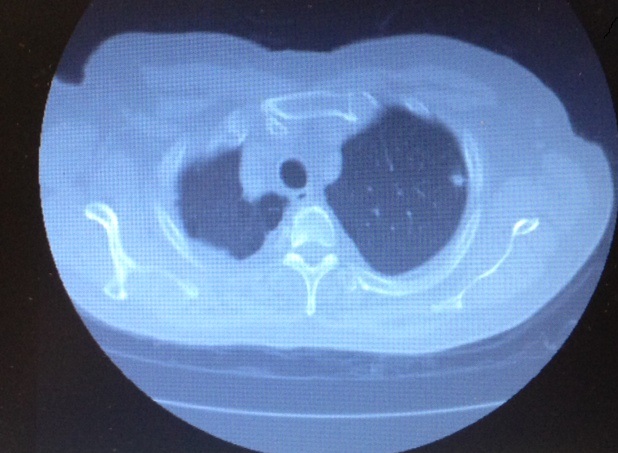

The left upper lobe has anatomically well-defined segments with a clear division of the hilar structures from the apical and lingular segments, allowing for an anatomical resection. The left apical tri-segments are the apico-posterior and the anterior segments of the upper lobe. These can be clearly isolated from the superior and inferior lingular segments, as the vasculature and airways are anatomically distinct from each other and can be clearly identified with surgical dissection. An alternate name for the operation is, therefore, lingular sparing left upper lobectomy (7). The lesion should be located well within the apical segments of the left upper lobe and be 1.5 cm or less in diameter. A CT scan is vital to aid in preoperative localization of the lesion and assessment of size and position within the lobe (Figure 1). Cross-sectional images, as well as coronal and sagittal imaging, should be used to confirm the position of the lesion, in addition to the vasculature and airway to the segments (6).

Figure 1: Anterior view of left hilum with phrenic nerve and pulmonary vein.